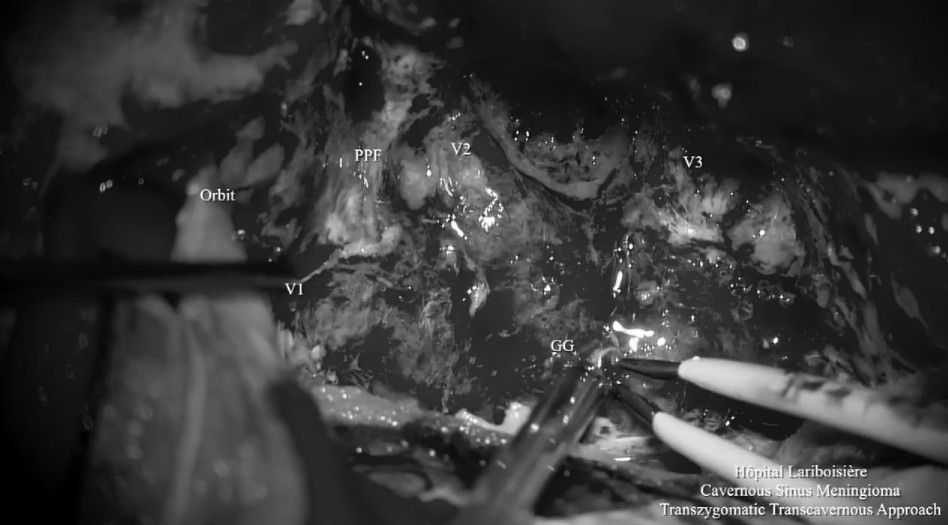

▼利用OPC间隙(orbitopterygopalatine corridor)进入蝶窦,发现肿瘤突出到窦内,暴露V2神经的侧面。神经内镜下对蝶窦中的肿瘤进行切除,这种方法可以切除硬膜内间隙和鼻窦中的肿瘤。为保留关键神经功能,海绵窦内的肿瘤没有切除。

▼切开眶肌

▼神经内镜操作下暴露和切除肿瘤